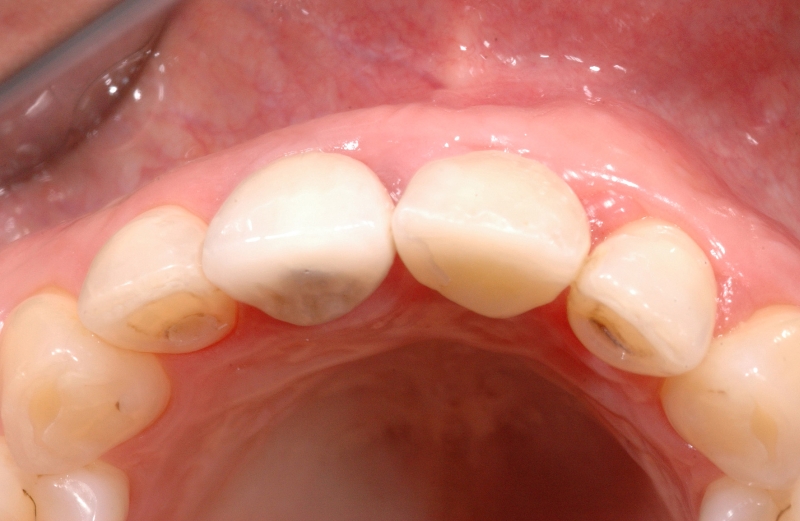

16/18 - Final restoration 15 months after implantation and stability of root coverage in regio 23GBR together with soft tissue augmentation with mucoderm® and maxresorb® - Dr. S. Scherg